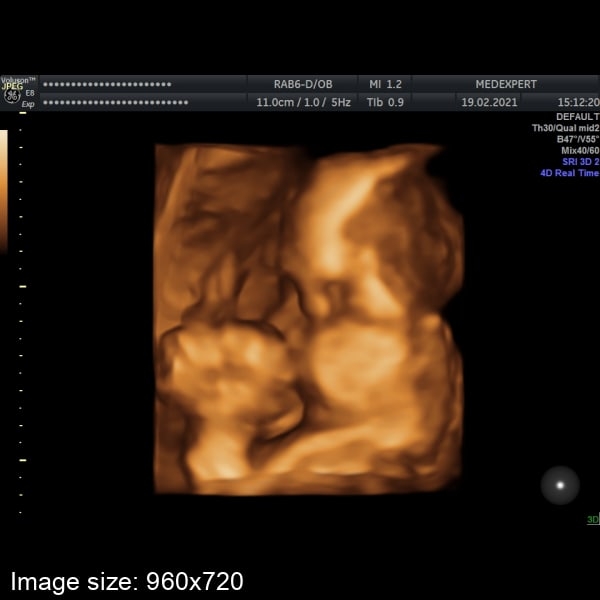

Вчера ходила на узи, сынок лежит головкой вниз, сердцебиение 134 ударов

Конечно чувствуется что малыш подрос, его вес ~1011гр.

Шла что бы увидеть личеко, но..все узи он прятался ручкой и не довал посмотреть 🤭